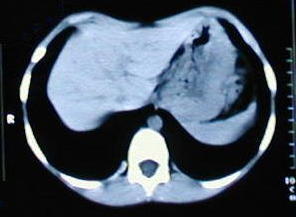

Tomografía de tórax

• Corte tomografico a nivel del tercio superior del torax, supracarinal.

• Corte tomografico a nivel carinal, comienza a insinuarse la depresión esternal.

• A medida que descienden los cortes, se observa la mayor depresión esternal.

• A nivel del tercio inferior se observa el punto de máxima depresion esternal.

• Corte a nivel del apéndice sifoides, observe la acentuada depresión por efectos de los cartilagos costales comunes.

• A nivel de la base del tórax los extremos de los arcos costales se observan protruyentes, debido al cambio de dirección de los cartílagos, ellos generalmente ceden, al resecar los cartílagos costales comunes.